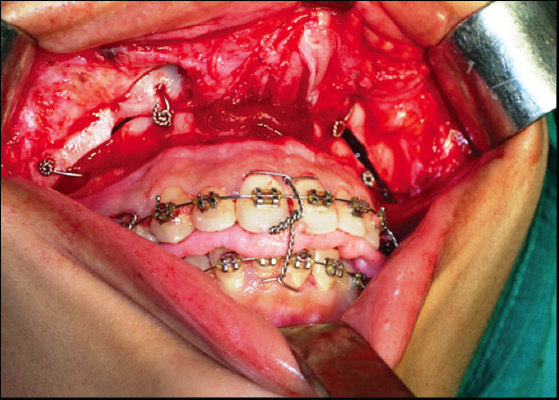

Patients in Group I were treated with wire fixation using 26-gauge stainless steel wire [Figure 1], and Group II received rigid internal fixation using titanium plates and screws [Figure 2]. Both groups underwent Le Fort I and anterior maxillary osteotomy to correct maxillary excess in the vertical and anteroposterior directions. Fourteen patients had underwent concurrent genioplasty for correction of chin deficiency.

thumb

Figure 1: Maxilla stabilized with wire osteosynthesis

Figure 2: Maxilla stabilized with rigid fixation